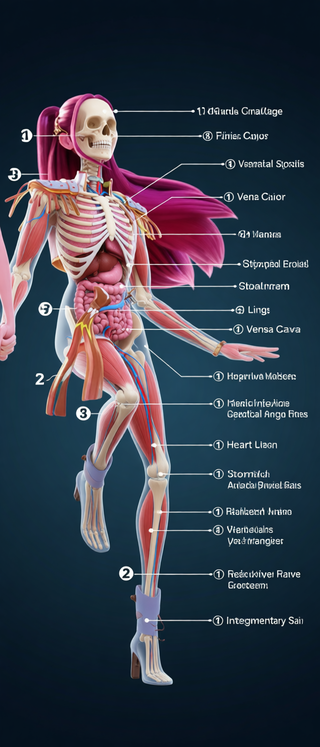

Creates ultra-detailed, multi-layer 3D anatomical visualizations from reference photos.Open

Creates ultra-detailed, multi-layer 3D anatomical visualizations from reference photos.Open

Transform photos into scientific anatomical illustrations.Open

Transform photos into scientific anatomical illustrations.Open